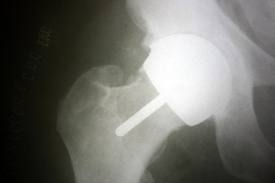

I had a Smith and Nephew Birmingham Hip Resurfacing in 2009 at age 39.

Finally toward the end of 2011 I began seeking other opinions. I was told by two different surgeons that the problems are evident on an x-ray and the BHR must be removed.